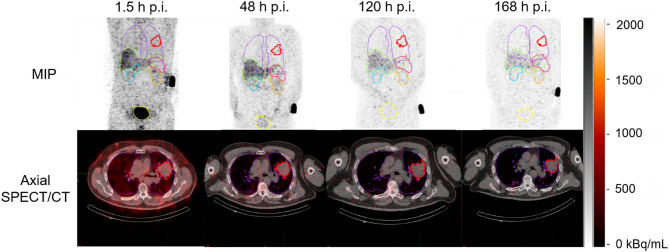

Background: Radiolabeled [195mPt]cisplatin has been developed as a tool to determine the biodistribution of cisplatin in vivo through SPECT imaging and possibly aid in patient-selection. This feasibility study aimed to evaluate the (radiation) safety, biodistribution, and image quality of [195mPt]cisplatin SPECT/CT in patients with non-small cell lung cancer (NSCLC). [195mPt]Cisplatin was produced under GMP standards. Six patients received 100 MBq [195mPt]cisplatin in their second or third week of chemoradiation therapy. Planar and SPECT/CT imaging were acquired at 1.5, 48, 120 and 168 h post-administration. Segmentation on SPECT for biodistribution and dosimetry was achieved using TotalSegmentator in 3DSlicer, and organ specific time-activity curves were generated through a mono-exponential curve fit. Effective and absorbed doses were obtained with S-values from IDAC-Dose 2.1. Toxicity was assessed using CTCAE criteria.

Results: Six NSCLC patients received 100.9 ± 3.3 MBq [195mPt]cisplatin at a radioactivity concentration of 11.1 ± 4.9 MBq/mL. No adverse events above grade 2 were observed. [195mPt]Cisplatin had a long retention time with an effective half-life of 74.8 h. Uptake was highest in the liver and kidneys, which also resulted in the highest absorbed dose at 48.6 ± 7.9 mGy and 38.4 ± 7.3 mGy, respectively. Tumor uptake was similar to blood, with a ratio of 1.0 ± 0.05.